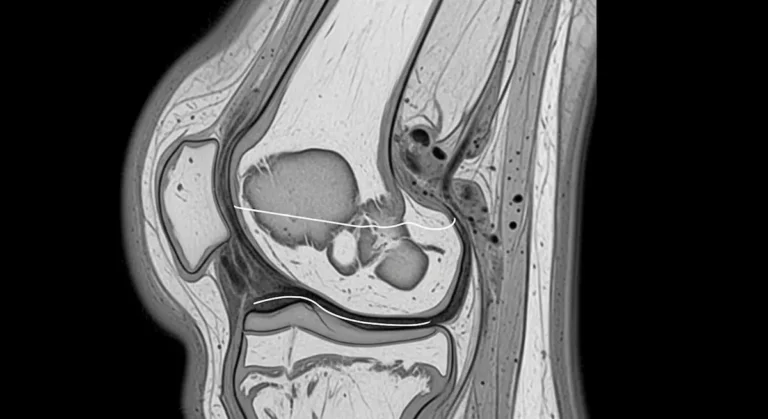

Cisto no menisco: o que é, sintomas, exames e tratamento

O cisto no menisco é um acúmulo de líquido que se forma junto a uma lesão meniscal. Essa alteração pode…